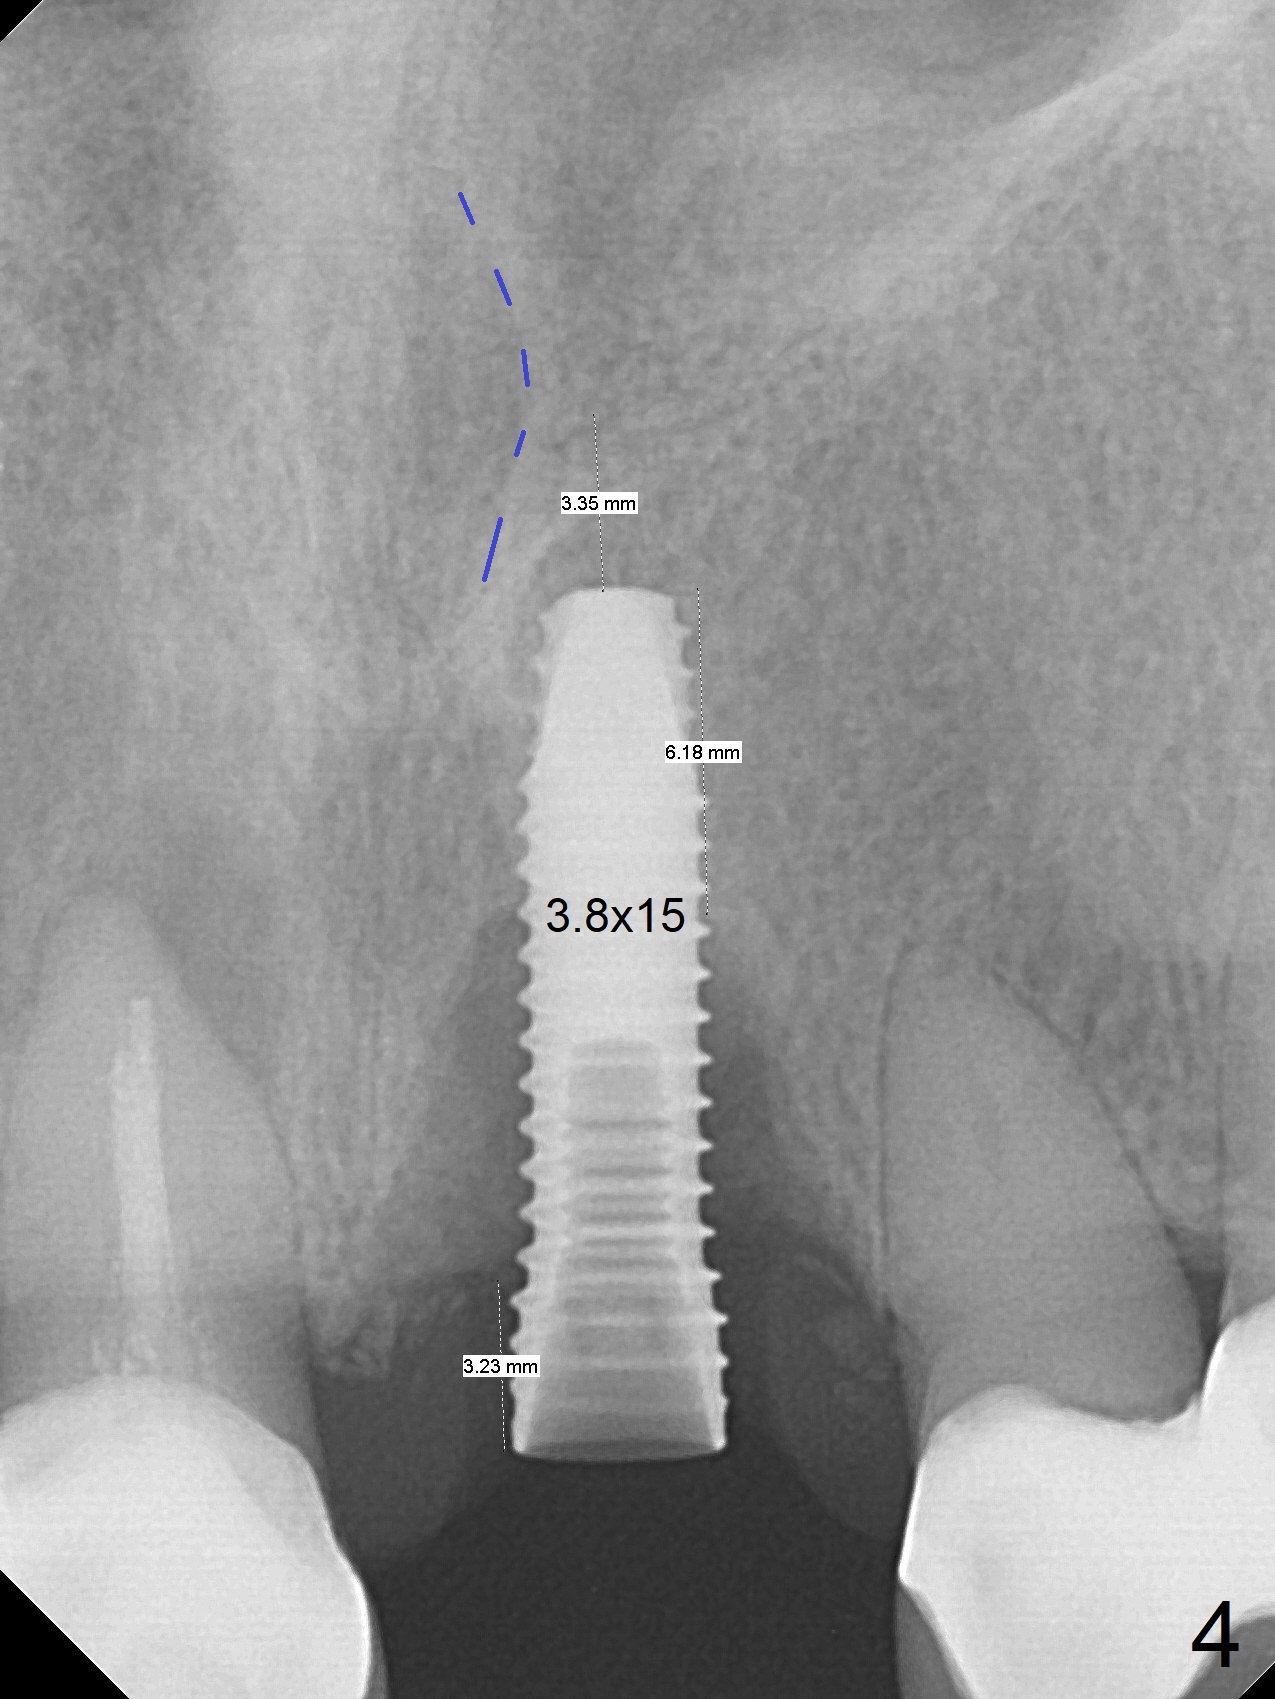

3.8x15 mm Implant with Proximity to

Nasal Floor

The buccal contour at #9 seems to be slightly concave preop (Fig.1,2 (*)). In fact the buccal plate is found to be lost when the tooth is extracted. Osteotomy is initiated as palatal as possible apical, but the occlusion dictates the coronal end of the osteotomy should be buccal, leaving the buccal gap ~ 2 mm for bone graft. The initial osteotomy (18 mm deep) appears to be close to the Incisive Foramen (Fig.3 blue dashed line). The nasal floor appears to be intact when the drill is removed. Subsequent osteotomy is adjusted so that the apical end of the osteotomy moves distal; when a 3.8x15 mm dummy implant is partially placed, there is clearance (Fig.4). It remains so when a definitive implant is seated (Fig.5); Vanilla graft is placed (Fig.5 *) before placement of a 4.5x5.5(3) mm abutment. More allograft is placed when an immediate provisional is fabricated (Fig.6 arrow and *). The gingiva remains to be recessive 1 month postop (Fig.7). It seems to be related to the bulky gingival margin of the provisional (Fig.8 *). After trimming the latter (Fig.9 *), the gingival margin immediately returns close to normal (Fig.10). The gingival margin is even between #8 and 9 two months postop, but the bone graft is exposed apically (Fig.11 ^). It may heals by itself. Otherwise debridement, regraft, PRF and suture are pending. The coronal portion of the socket heals 4 months postop (Fig.12). The gingival cuff forms by the immediate provisional (which is removed for impression) 4 months postop (Fig.13 *). While the full Zirconia crown at #7 remains intact (Fig.14), the PFM at #9 has porcelain chip (Fig.15). It is partially due to the occlusion; while the crown at #7 has clearance with the opposing dentition (Fig.16 *), the one at #9 has no. The access hole at #9 (Fig.17 *) seems to weaken the crown structure. There is no access hole at #7. No solid posterior support is another contributing factor for chip (Fig.18). The buccal plate has mild atrophy at #7 and 9 (Fig.19 *). A piece of bone graft is being expelled apically at #9 (Fig.20 >) and is removed subsequently (Fig.21). Before impression for repacking porcelain, the opposing incisal edge has been shortened (Fig.22 arrows, as compared to Fig.16). Since the ideal access hole is at the incisal edge (Fig.25 black circle), buccal to the existing one (Fig.24 A), the abutment is torqued before the repaired crown is recemented (Fig.23). Finally the crown has occlusal clearance (Fig.26). Porcelain chips again around the access hole of PFM 1.5 years post 2nd cementation. The dense bone at the crest (*) cannot explain why the abutment is not loose, since it remains incompletely seated (>). As it was trimmed short, an angled abutment is used (Fig.28). The coronal end is lingual, while #9/24 is edge to edge. The lingual aspect of the coronal end of the abutment is heavily trimmed to reduce bulkiness. To prevent chip, Zirconium crown will be fabricated in spite of the fact that it does not match the PFM of #8 (potential shade discrepancy). The patient is pleased with the new Zirconia crown (Fig.29).